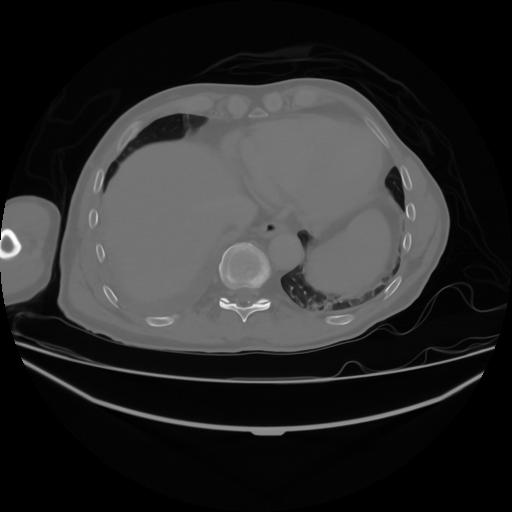

4 CUERPO,CE,Axial,3.0,CUERPO,,